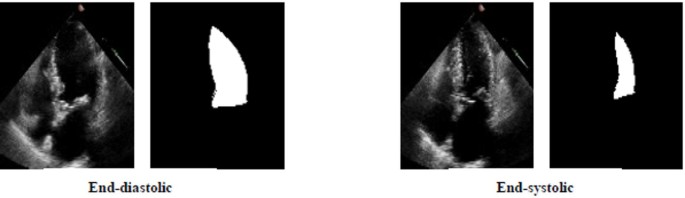

The CAMUS dataset contains echocardiography examinations from 500 patients, acquired at the University Hospital of St Etienne, France39. It is intentionally heterogeneous, including images of varying quality and multiple pathological cases. The data is split into a training set of 450 patients and a testing set of 50 patients. For each patient, data from both end-systole and end-diastole phases are provided with ground truth segmentation masks for the LV cavity. While the dataset includes multiple views, we utilized only the apical-4-chamber (A4C) images in this study to maintain consistency with EchoNet-Dynamic. The original ground truth masks were multi-class and were converted to binary masks during our preprocessing stage. The details of EchoNet-Dynamic are summarized in Table 3, and Fig. 3 shows a sample image of this dataset.